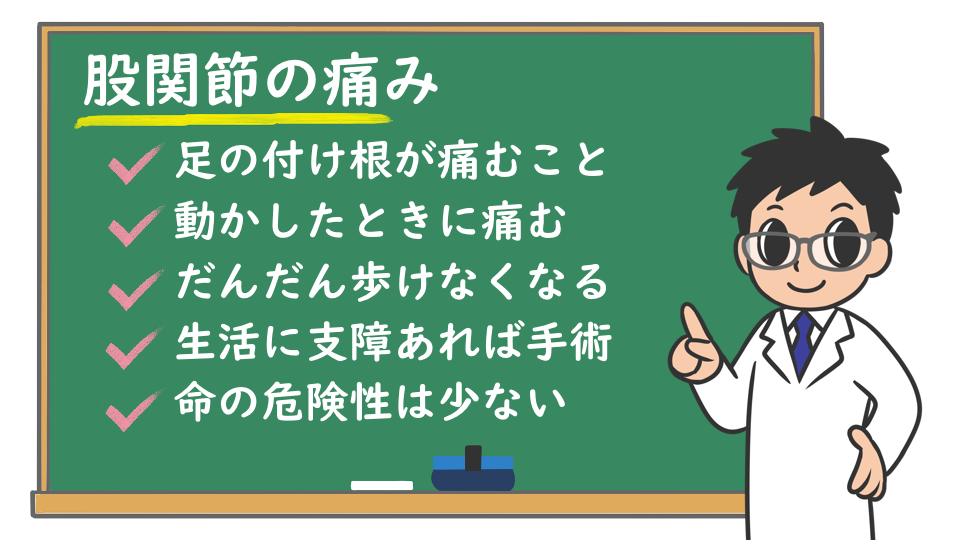

⑤ 痛みが続く場合の考え方|来院を検討する目安

・「様子見」でよい痛みと、注意したいサインの違い

「セルフケアをしているけど、まだ違和感が残る…」

そんなとき、どこまで様子を見ていいのかは迷いやすいポイントです。

一般的には、

「休むと少し楽になる」

「日ごとに重だるさが減っている」

といった変化があれば、経過を見てもよい場合があると言われています。

一方で、

「数日〜1週間以上たっても変わらない」

「動かしていないのにズキズキする」

「可動域が明らかに狭くなった感じがある」

といった状態が続く場合は、体の中で別の要因が関係している可能性も考えられているそうです。